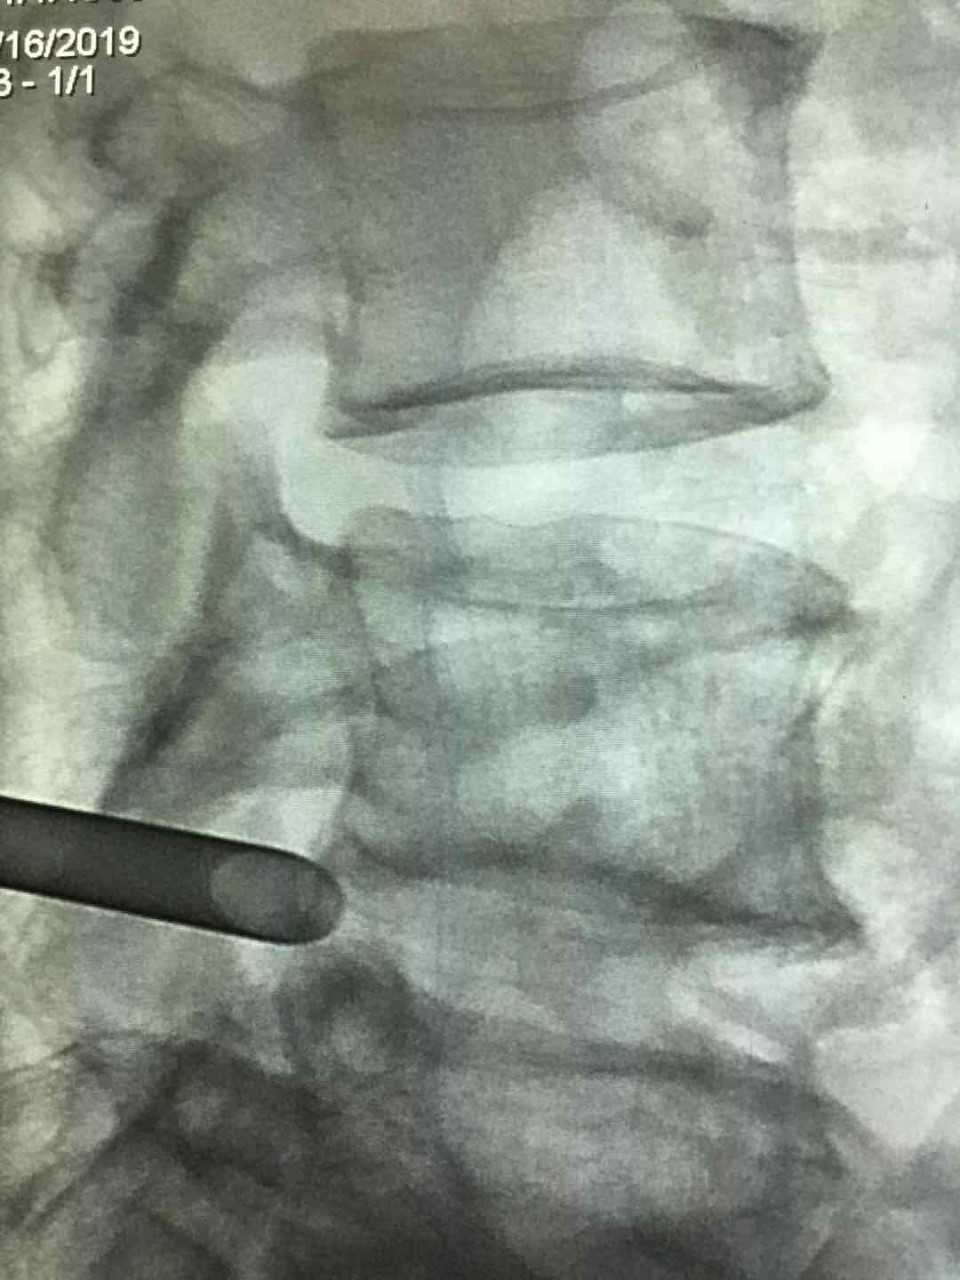

精确工作套管放置

家住合肥的患者陈某今年60岁,5月初,陈某搬重物后突然出现腰及右下肢疼痛剧烈不能行走,活动后加重。曾接受保守治疗暂时控制住病情,也自己用膏药敷贴缓解疼痛, 但效果不佳。陈某遂赴省城多家医院就诊,MRI示椎间盘膨出。腰椎退变。药物及康复治疗两天后症状加重。5月10日,陈某及家人随即来到安医大一附院疼痛科就诊。经精确诊断后确诊为极外侧型巨大椎间盘突出。这是非常少见的一种椎间盘突出类型,存在30%的误诊率。入院后陈某对传统腰椎间盘手术抱有极大的恐惧心理。一是担心手术疼痛,二是担心会造成神经损伤之类的并发症。疼痛科副主任医师宋阳通过和陈某对椎间孔镜手术详细介绍后,陈某同意手术。术前给患者做了椎间盘造影,更加准确定位突出位置和节段。术中局部麻醉完善,整个手术患者没有任何不适感觉。且可以清醒的和手术医生交流手术的疑惑。术中医生通过高清显像系统向陈某实时解释了手术目的及效果体现。在清醒舒适的状态下医患共同参与了手术过程,取出巨大椎间盘突出近7cm。如此巨大的极外侧型椎间盘突出实属罕见。

术后,陈某一天后即可下床活动,三天出院。快速康复。整个医疗过程体现出现代疼痛微创技术的三大优势:1. 精准医疗。从术前诊断到术前造影定位到术中靶向放置工作套管到术中精确减压。2.舒适化医疗。整个过程基本无痛。3. 微创化医疗。除去突出物摘除,不破环正常骨质,韧带,脂肪组织。